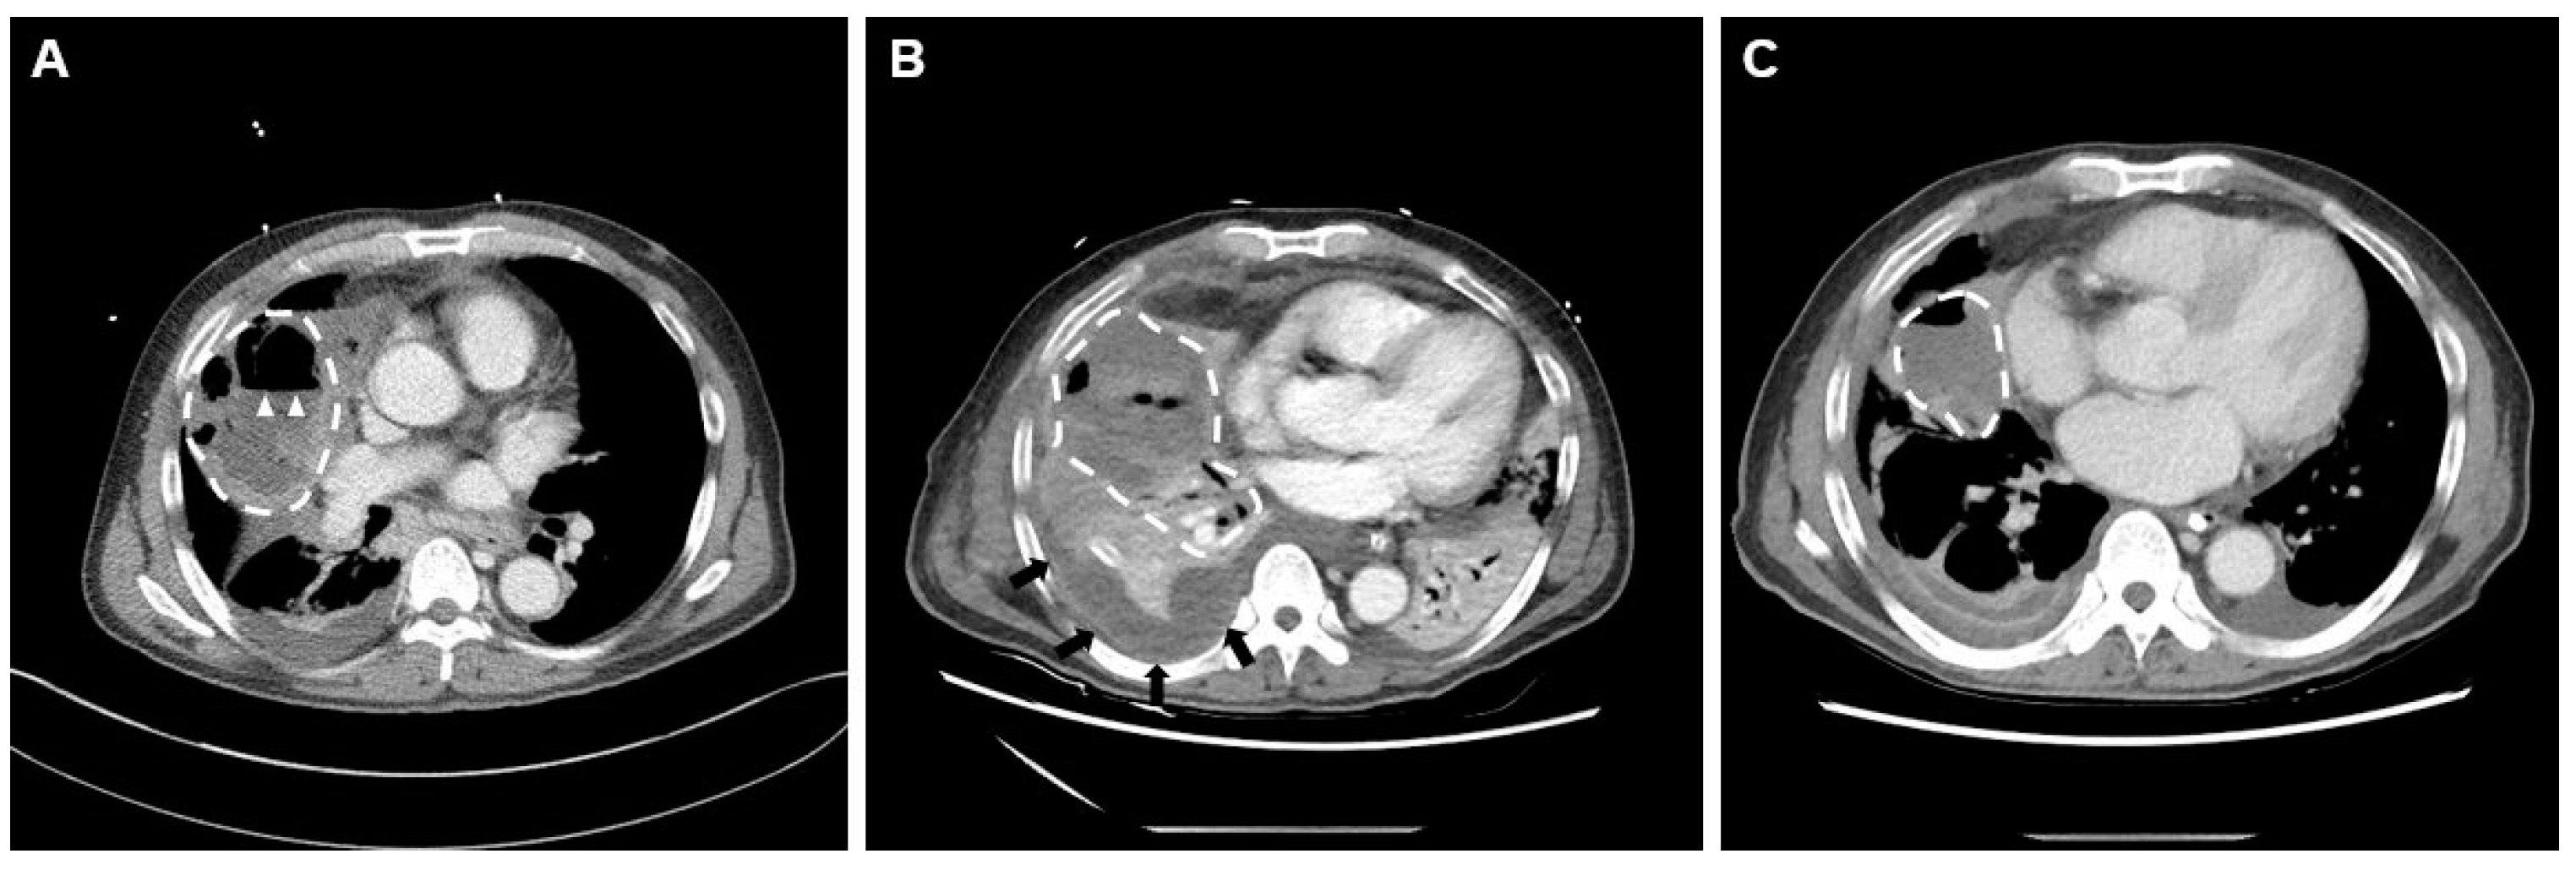

2. Case Presentation